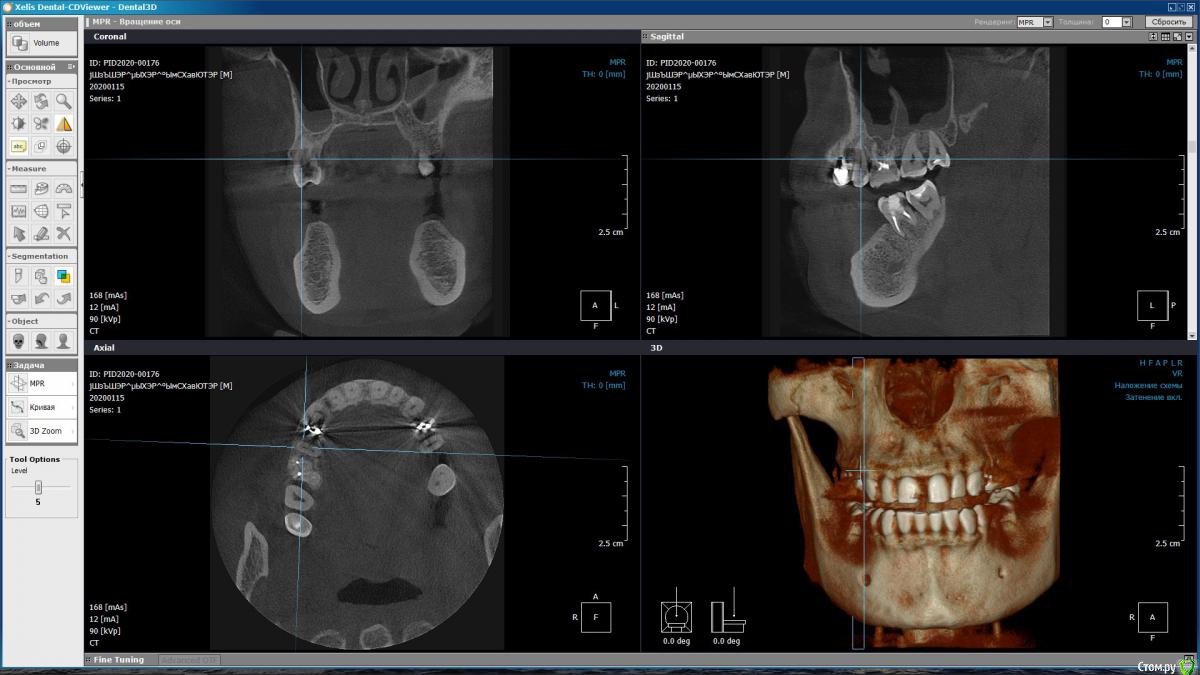

m-e-a Опубликовано 19 января, 2020 Автор Поделиться Опубликовано 19 января, 2020 (изменено) Сделала срезы как смогла, не умею я смотреть КТ Изменено 19 января, 2020 пользователем m-e-a Ссылка на комментарий

red_butler Опубликовано 19 января, 2020 Поделиться Опубликовано 19 января, 2020 На представленных срезах, показаний к удалению не увидел. Нужно смотреть очно и «крутить» Кт Ссылка на комментарий